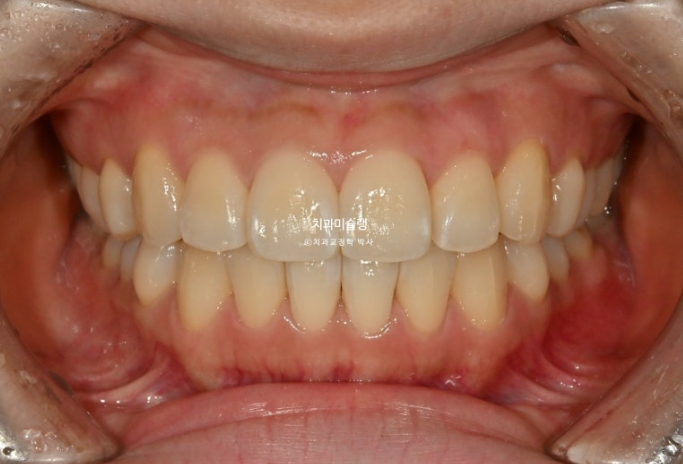

중심선은 완벽히 맞으며 앞니 배열과 높낮이는 교과서적입니다.

원래 좋았던 어금니 교합은 잘 유지되었습니다.

이제 전후비교 볼게요. 총 치료기간은 9개월입니다.

25.03~25.12

유지장치까지 들어간 모습입니다.